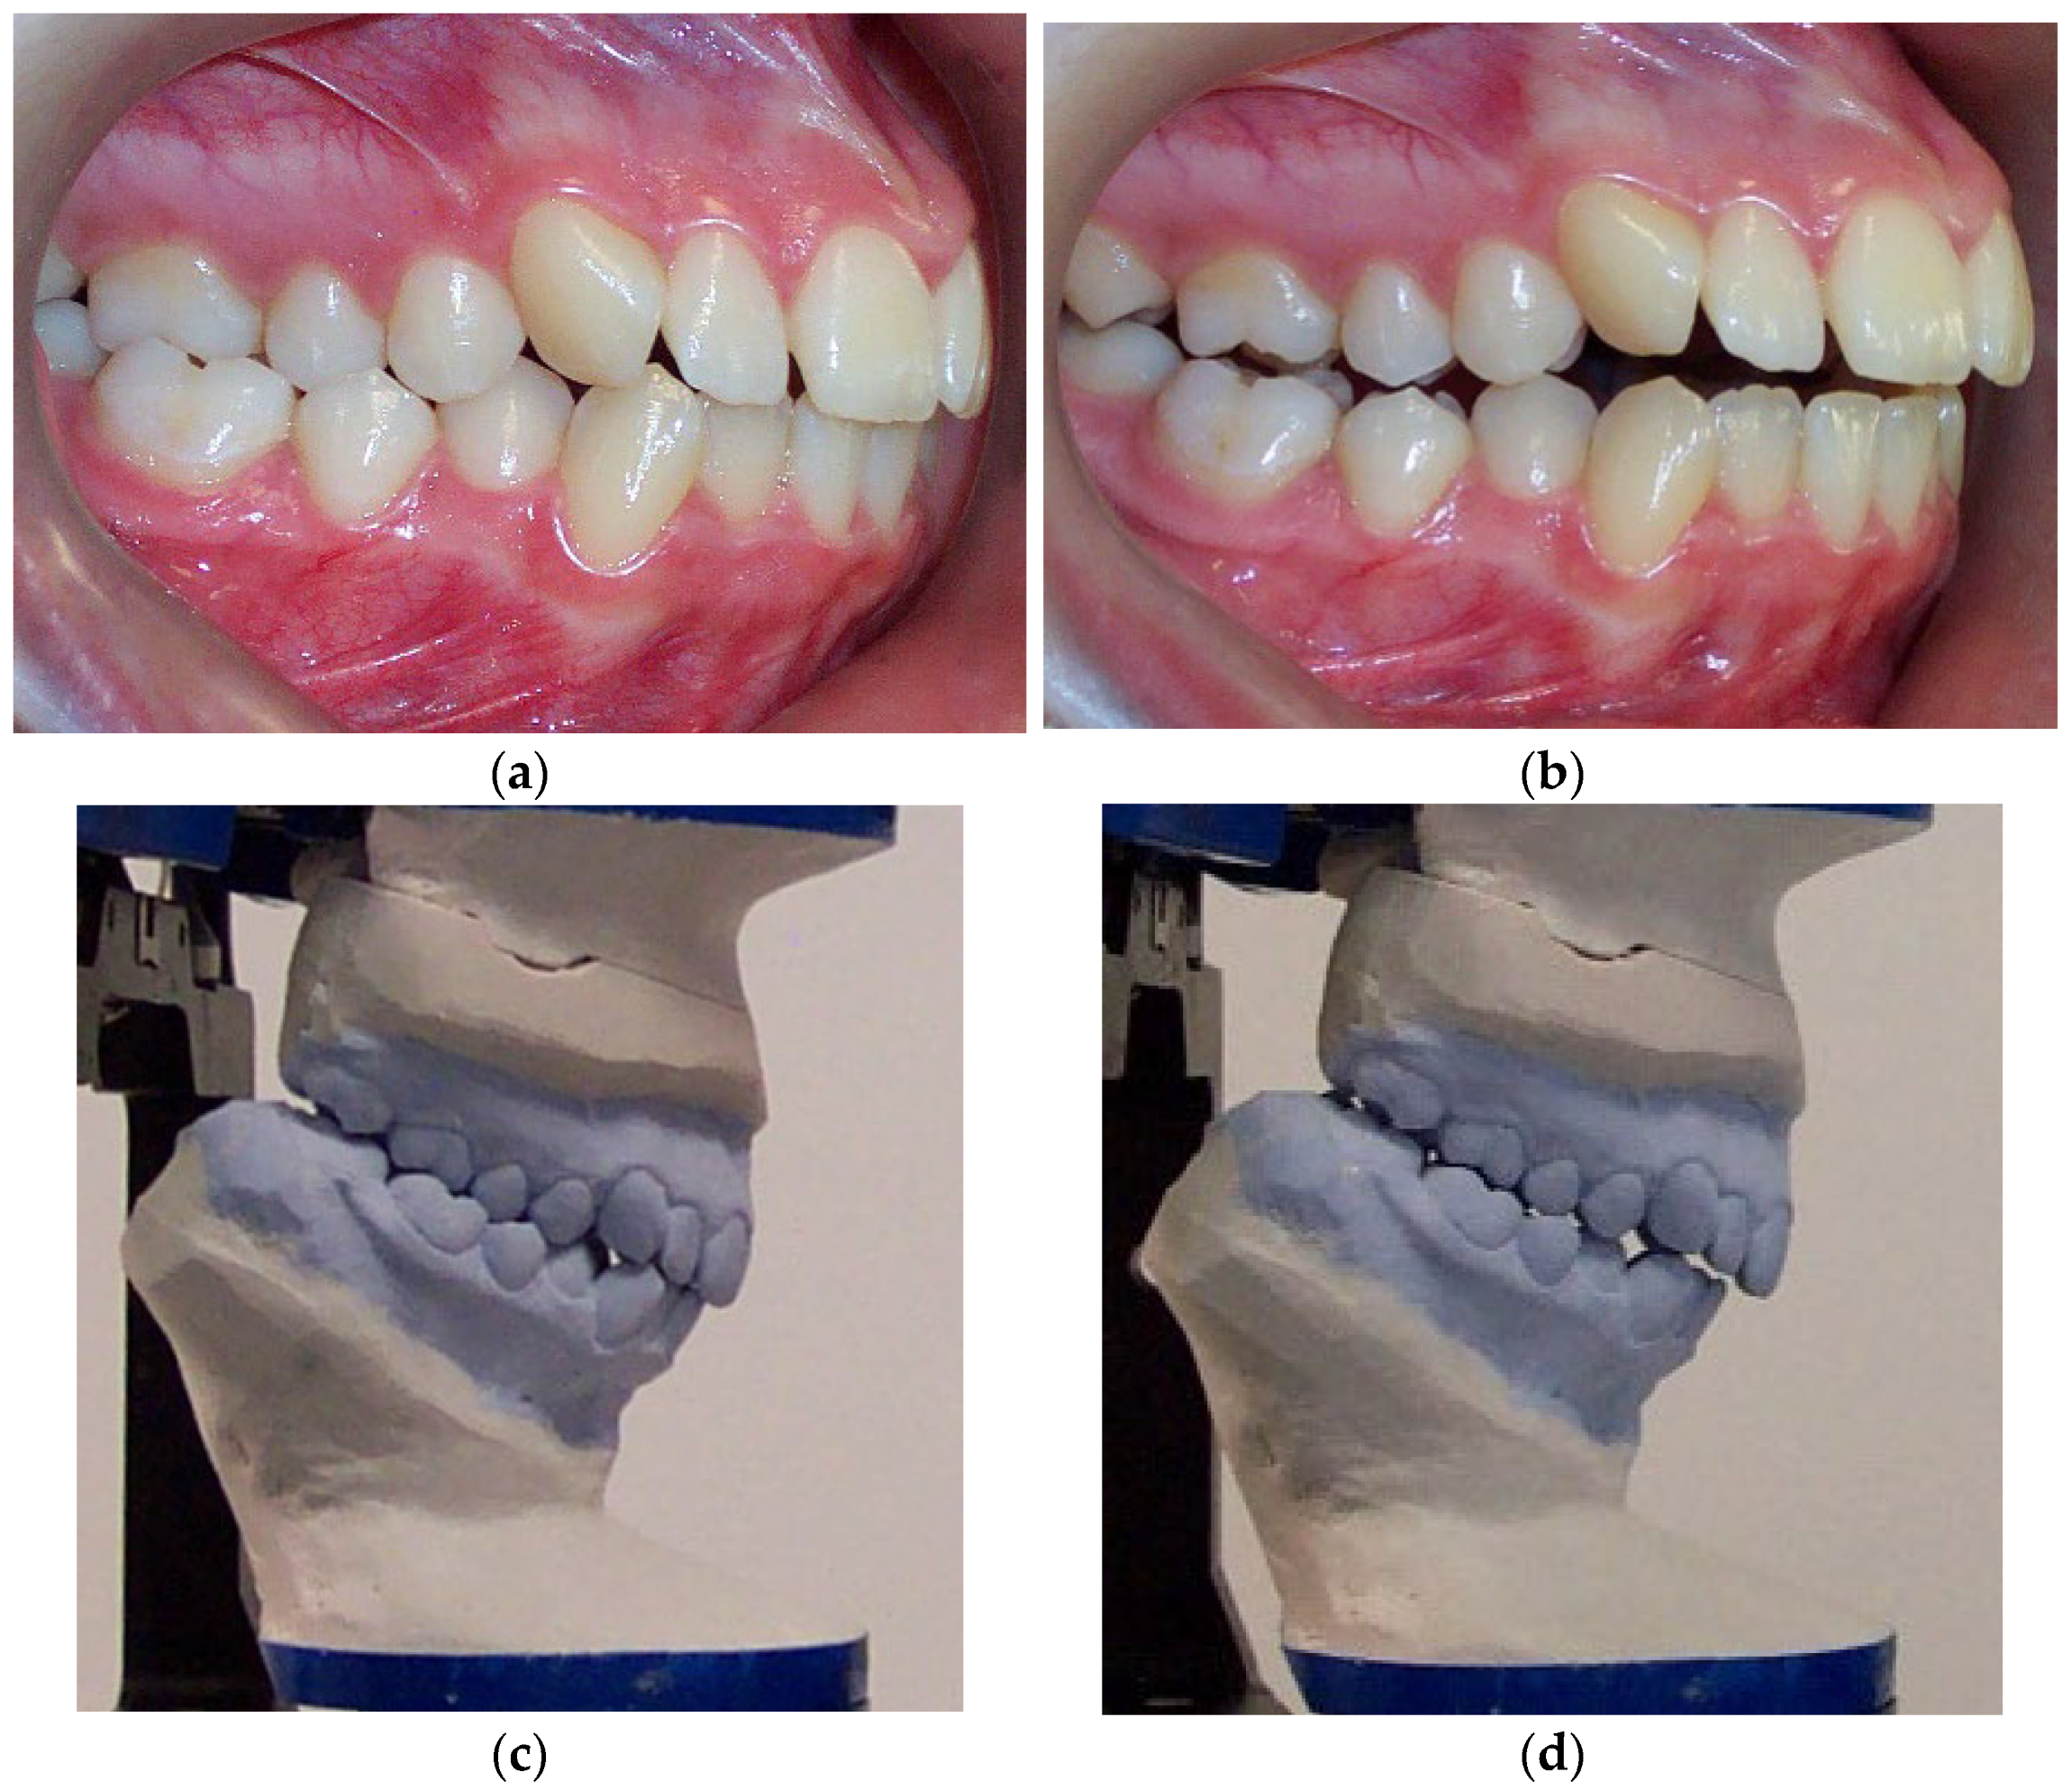

2. Materials and Methods

2.1. Subjects